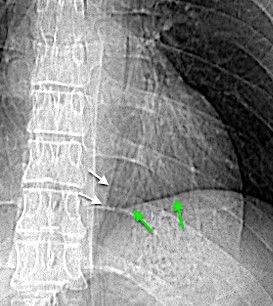

Empiema pleural izquierdo. Absceso del LID. Espondilodiscitis D11-D12.

Potsios C et al. Pyogenic Spondylodiscitis due to Streptococcus constellatus in an Immunocompromised Male Patient: A case Report and Review of the Literature. Case Reports in Infectious Diseases. 2019